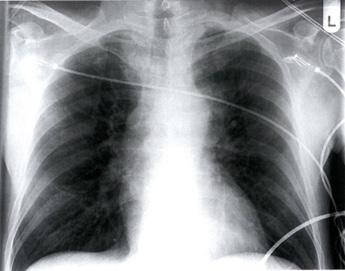

Radiografía de tórax → silueta cardíaca agrandada con campos pulmonares claros → Signo de la botella de agua

Figura 25. Ecocardiograma en taponamiento cardiaco, nótese colapso de la aurícula derecha Figura 26. Derrame pericárdico con configuración de botella de agua Figura 27. Abordaje subxifoideo Figura 28. Abordaje paraesternal izquierdo Figura 29. Abordaje apical